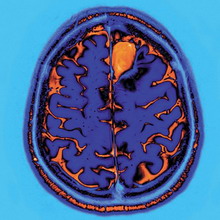

Протокол разделен на 4 этапа. 1) Обучение. Перед началом занятия выполняли 2 строки на бумаге вместе с экспериментатором. Затем задача на компьютере с этапом обучения, состоящим из 10 испытаний которые содержали скрытое правило. 2) Предварительная фаза. После обучения пройти 2 блока по 30 задач. 3) 20-минутный перерыв. Полусидячее положение на стуле в темной комнате, с закрытыми глазами и ногами на подставке для ног. Держали пустую бутылку в правой руке. Пытались расслабиться или поспать. Что может быть лучше? Сон, эротика, массаж. Если засыпали и бутылка падала во сне, и звук будил их, они брали ее и повторяли процедуру до конца перерыва. Активность мозга регистрировали с помощью электроэнцефалографических шлемов. Они измеряют электрические волны от нервных клеток, позволяют фиксировать N1 и N2. 4) Пост-этап. Через 10 минут после пробуждения выполнили пост-сессию, которая состояла из 9 блоков по 30 попыток в каждой (всегда содержавших регулярность) и продолжалась в среднем 64 мин.